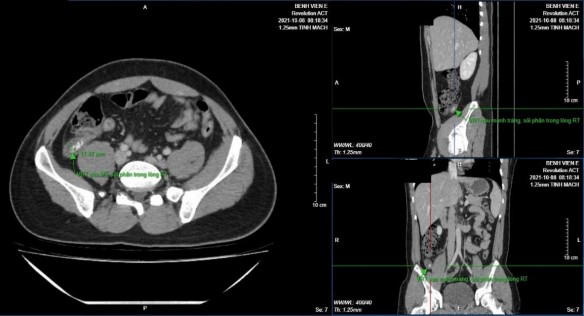

Hình 3.3: Ruột thừa ở vị trí sau manh tràng, trong lòng có sỏi phân

Bệnh nhân Hoàng Công M. 27 tuổi, mã bệnh án 2120143. GPB VRTC.